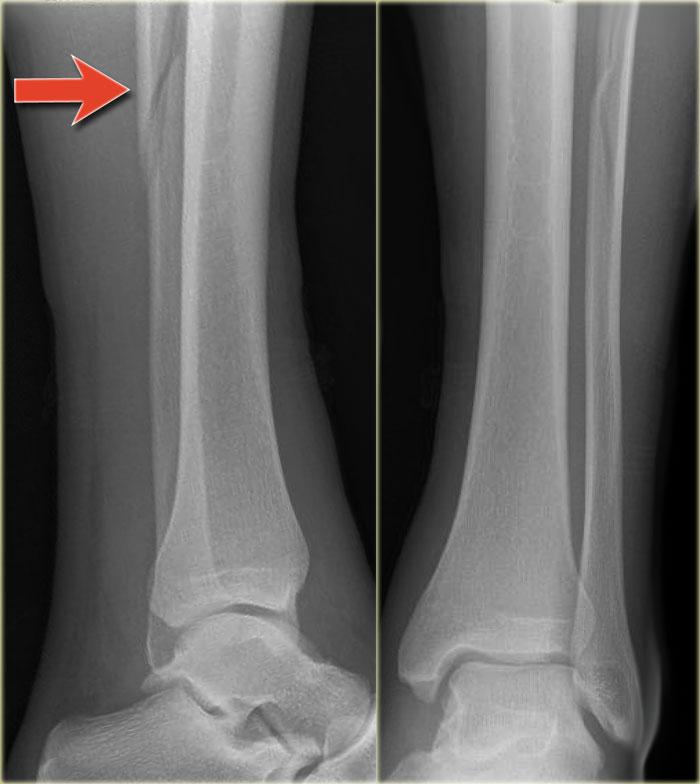

Bệnh nhân này bị lật cổ chân và bất thường duy nhất được thấy trên tư thế nghiêng.

Tổn thương này được cho là bong điểm bám mắt cá sau.

Biết rằng đây có thể là dấu hiệu duy nhất của gãy Weber C cao, các phim X-quang bổ sung đã được chụp.

Tiếp tục xem hình ảnh cẳng chân.

Có thể thấy một đường gãy xương mác cao kín đáo (mũi tên).

Chẩn đoán cuối cùng là gãy Weber C hoặc theo phân loại Lauge Hansen: chấn thương xoay ngoài – sấp giai đoạn 4.